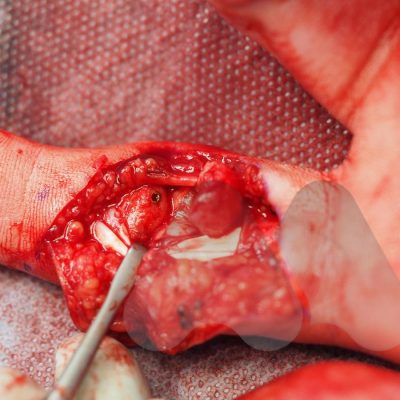

Depending on the location of the fracture, type of bone and blood supply, will determine whether non surgical immobilisation or surgery is recommended.

If fractures of the hand, wrist, elbow and shoulder require a specialist referral, this should normally be seen within a week of injury. If required, surgery within 2 weeks of injury usually allows for the best outcome. Prolonged delays in accessing surgery can increase the complexity and risks of surgery and in some cases it may be better to allow the fracture to heal and allow corrective surgery at a later date (corrective osteotomy).